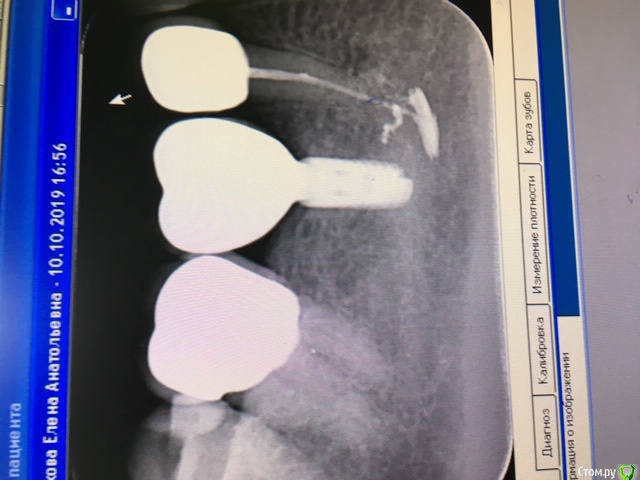

Elena2011 Опубликовано 22 ноября, 2019 Поделиться Опубликовано 22 ноября, 2019 Доброе утро, уважаемые специалисты! Подскажите пожалуйста, как быть.В начале августа при пломбировании канала временный материал метапекс вышел за пределы канала. Было онемение подбородка и нижней губы, покалывание в этой части лица. Сейчас онемение практически прошло, покалывания редки. Зуб накрыт коронкой на временном цементе, рядом установлен имплант.Спустя три месяца снимок показал, что ничего не рассосалось, пломбировочный материал остался в неизменном виде. Уважаемые врачи, помогите, как быть?Ждать дальше, не ставить коронку на постоянный цемент?Удалить этот вышедший материал? Чем вообще эта ситуация грозит? Снимок прилагаю, благодарю!!! Ссылка на комментарий